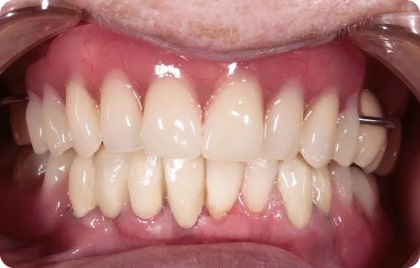

Зубы за 1 день за 5776р. в месяц

с пожизненной гарантией

По уникальной методике

БЕЗ отёков и надрезов

Установка

за 1 день